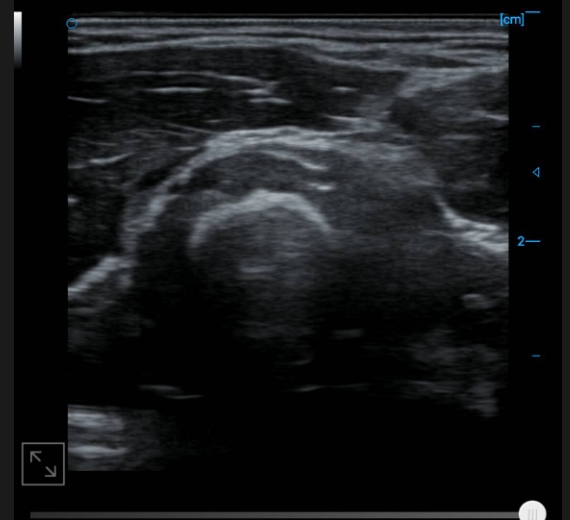

B-image of upper forearm cross-section

Finger extensor tendon B image

A1 Trochlear and joint recess B image

Finger flexor tendon B image

Image of flexor digitorum profundus tendon B

Image of lateral collateral ligament B